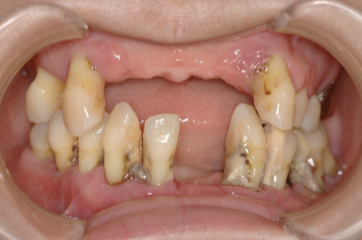

| 主訴 | 歯がグラグラで噛むことができない。インプラントをして欲しい。 |

| 治療内容 | 歯周病で骨の吸収が重度で保存不能なため抜歯、仮の入れ歯を作り、6ヶ月の抜歯窩の治療の後に、インプラントのCTによる診査診断を行い、下顎に6本インプラント埋入と同時に仮歯を入れる。その後、上顎は8本のインプラント埋入と同時に仮歯を入れる。左右上6はソケットリフトによる上顎洞拳上術を行う。その後免荷期間6ヶ月待ってセラミックを用いた上部構造作製、装着しメンテナンスに移行する。 |

| 治療費 | 9,000,000円(税込) |

| 治療期間 | 2年3ヶ月 |

| 治療回数 | 90回 |

| 想定されたリスク | 重度の歯周病により無歯顎になったため、プラークコントロール不良による、術後のインプラント周囲炎が懸念される。歯冠の部分はセラミックなため欠ける可能性がある。 |